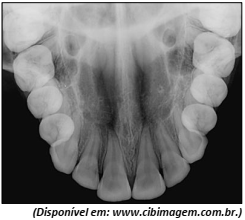

Observe a imagem.

Qual é o tipo de radiografia apresentada?